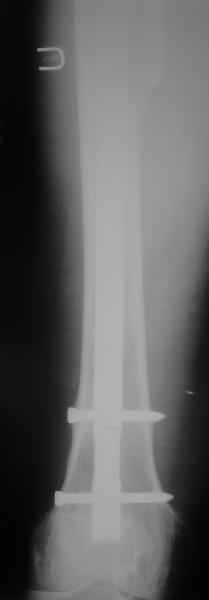

[Ortho] Перипротезный перелом

Пациента удалось осмотреть недавно. Достигнутый результат сохраняется.

Перелом бедра сросся. Конечность опорная и безболезненная, ходит без

трости. Ножка, похоже, реинтегрировалась, как и надеялись.

Снимки и фото в приложении.

Надо ли что-то делать дальше, как полагаете? Убрать винты? Убрать

"удлинитель ножки"? Или оставить все, как есть? Спасибо заранее.